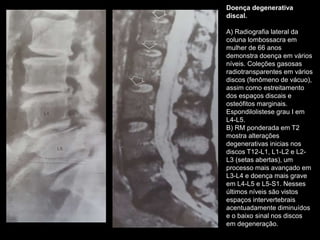

Doença degenerativa

discal.

A) Radiografia lateral da

coluna lombossacra em

mulher de 66 anos

demonstra doença em vários

níveis. Coleções gasosas

radiotransparentes em vários

discos (fenômeno de vácuo),

assim como estreitamento

dos espaços discais e

osteófitos marginais.

Espondilolistese grau I em

L4-L5.

B) RM ponderada em T2

mostra alterações

degenerativas inicias nos

discos T12-L1, L1-L2 e L2-

L3 (setas abertas), um

processo mais avançado em

L3-L4 e doença mais grave

em L4-L5 e L5-S1. Nesses

últimos níveis são vistos

espaços intervertebrais

acentuadamente diminuídos

e o baixo sinal nos discos

em degeneração.